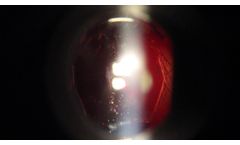

The benefits of True Coaxial Illumination, TCI, extend beyond the safe treatment of floaters, and in fact help to prevent the notoriously common patient complaint of sudden floater development after capsulotomy. In this video Dr. Paul Singh shows how TCI can be used to combat the remnants which can appear post-capsulotomy, using Ellex’s Reflex Technology ...